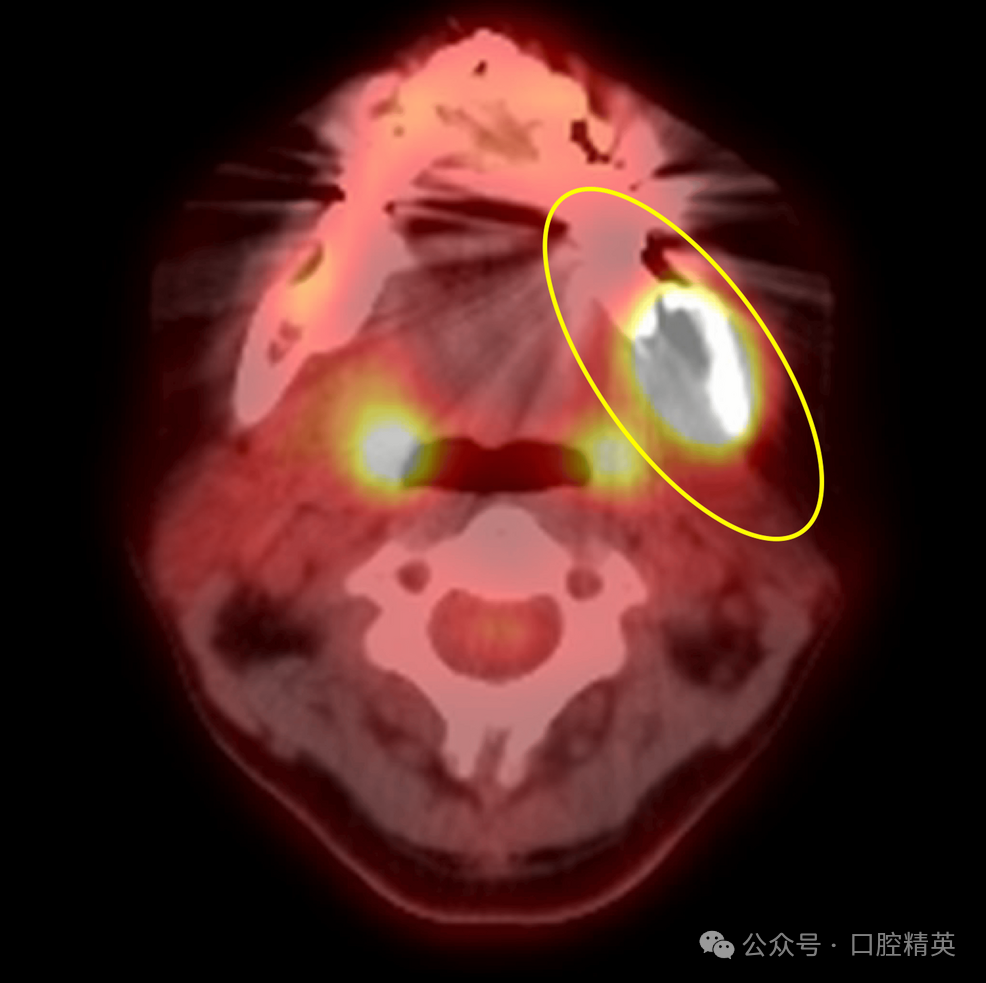

2017年3月,一名53岁女性因左下第三磨牙区疼痛就诊于当地牙科诊所,临床诊断为左下第三磨牙冠周炎,转诊至我科拟行拔牙术。初诊时,患者口外检查未见异常;口内检查见左下磨牙区牙龈红肿,左下第三磨牙(38)完全阻生。曲面体层片显示36、37牙根尖区可见少许低密度影,但38周围无明显异常(图1)。

图1 初诊曲面体层片

可见36、37根尖区少许低密度影,38周围无显著异常(黄圈所示)。